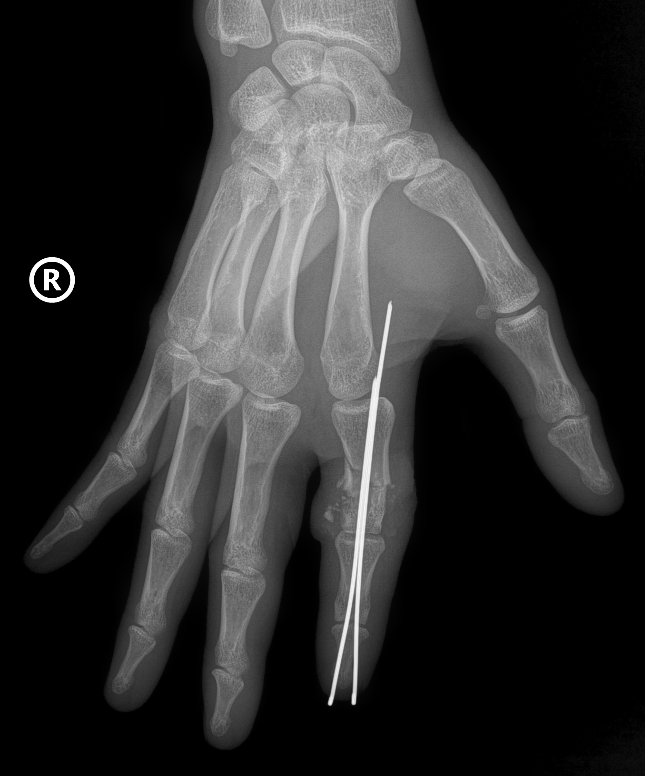

Tại phòng mổ, kíp phẫu thuật cấp cứu được triển khai với sự phối hợp đa chuyên khoa: vi phẫu tạo hình, gây mê hồi sức, chấn thương chỉnh hình… Hai kíp phẫu thuật được triển khai song song, một kíp làm sạch và chuẩn bị phần ngón đứt rời, kíp còn lại chuẩn bị phần mỏm cụt. Xương ngón được định vị và cố định bằng kim chuyên dụng để tạo trục vững, hệ thống gân và dây chằng được phục hồi. Đặc biệt là thần kinh và các mạch máu nhỏ li ti chỉ khoảng 0,8 - 1mm được phục hồi với độ chính xác cao dưới kính hiển vi phẫu thuật với dụng cụ đặc biệt nhằm đảm bảo phục hồi lưu thông tưới máu cho phần đứt rời.

| Hình ảnh X-Quang phần ngón trỏ tay phải bị đứt rời của anh D được định vị và cố định bằng kim chuyên dụng |